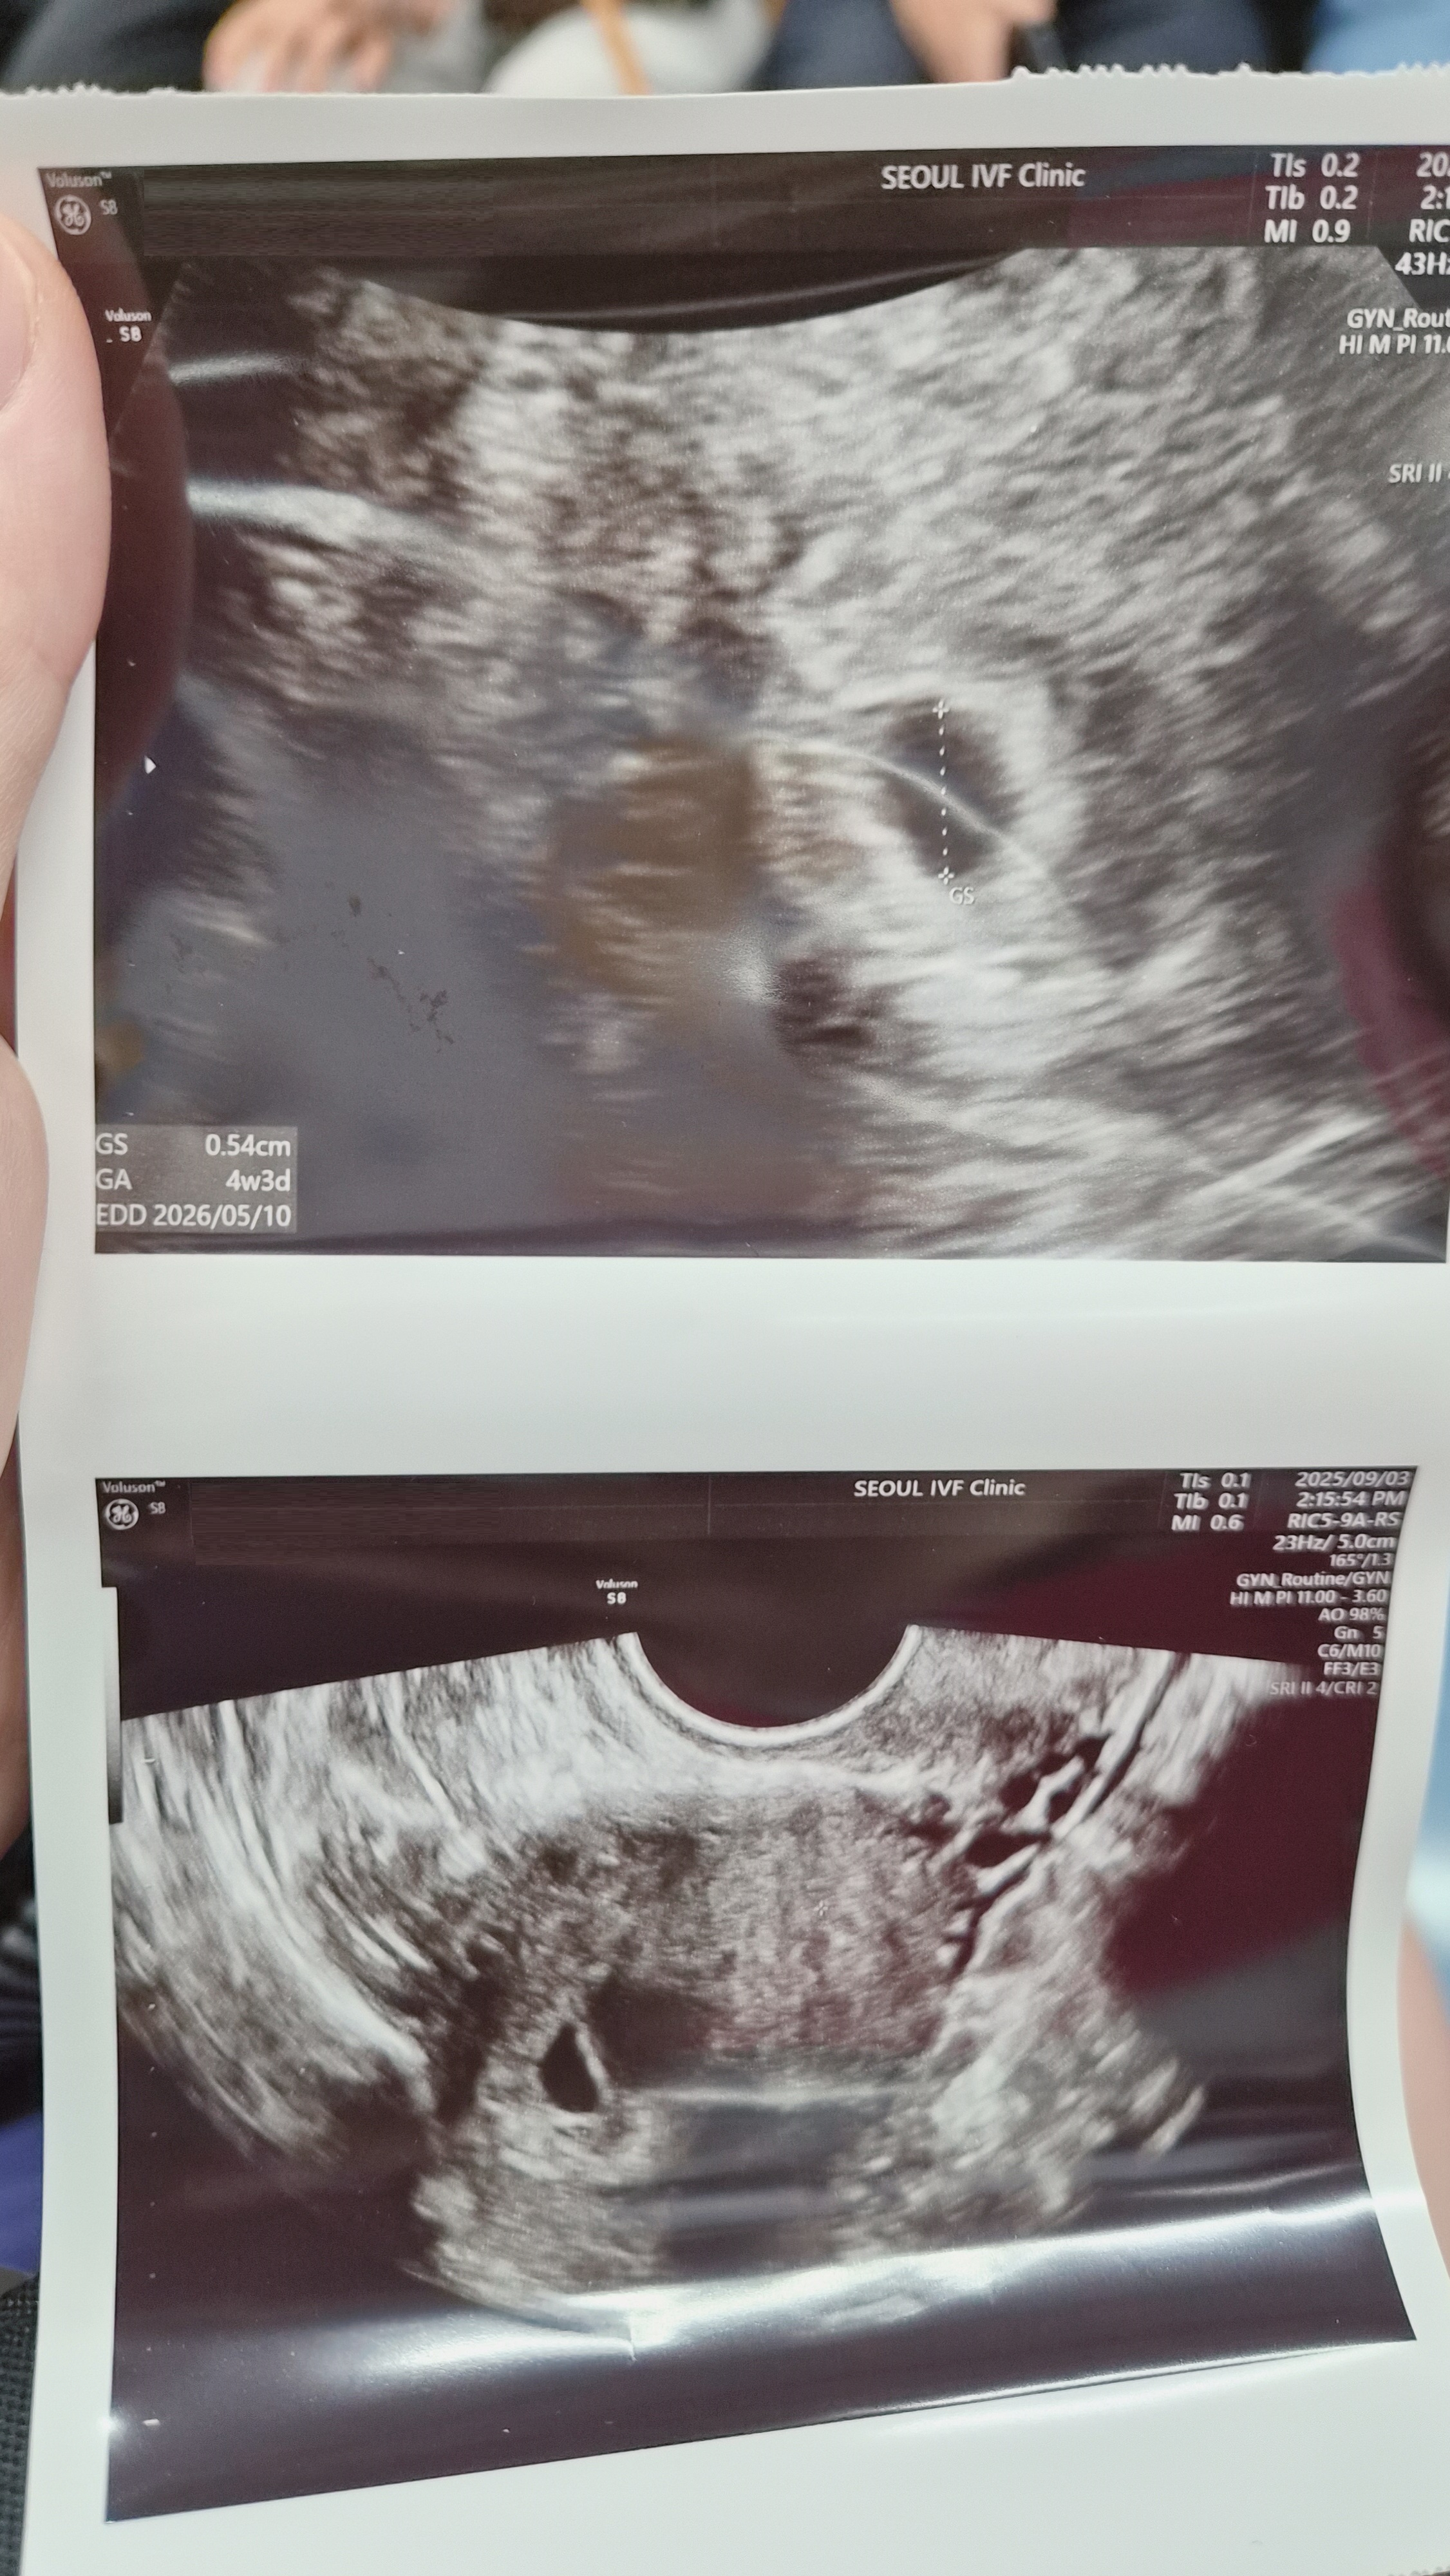

| 가슴 떨리는 임신 이야기를 공유해 주세요. | 5일배양 이식 후 3일차에 어렴풋이 두 줄이 보였던 그 순간, 처음에는 ‘설마.. 아니겠지…’ 하며 믿지 못했지만 임테기가 점점 진해지는 걸 보며 드디어 임신했다는 확신이 들었어요. 기쁘다기보다는 이 아이를 꼭 지켜야 한다는 마음이 더 강하게 들었던 순간입니다. |

| 치료 도중 느꼈던 가장 기뻤던 순간과 절망적인 것들은 무엇인가요? 잊지 못할 경험이 있나요? | 처음 임신 확인을 피검사로 했는데, 그 날을 절대 잊지 못합니다. 수치가 49로 아주 높진 않았기에 기쁨과 걱정이 동시에 밀려왔어요. 절망적이었던 순간은 난자채취에서 10개나 채취되었는데 수정란이 1개뿐이라는 결과를 들었을 때였어요. 이번에 실패하면 다시 난자채취를 해야 한다는 사실이 너무 힘들게 느껴졌습니다. |